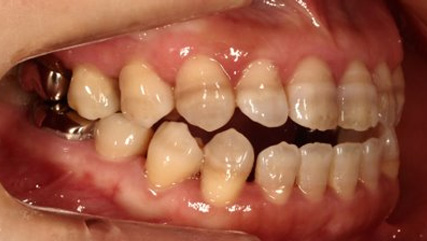

治療前

治療終了前

乱ぐい歯、でこぼこがとても酷い状態になります。歯が前後的に重なってしまっている、八重歯になっているなどがこのジャンルに入ります。

顎の大きさと歯の大きさのギャップが大きく、時には歯を抜かないと矯正治療ができない場合もあります。当院では治療期間が長くなるが抜かない治療方針など、一つの治療プランだけでなく、さまざまな可能性の治療方針を説明させて頂くよう心掛けております。こういった考え方はインフォームド・チョイスと言われ近年大切にされている考え方と言われております。